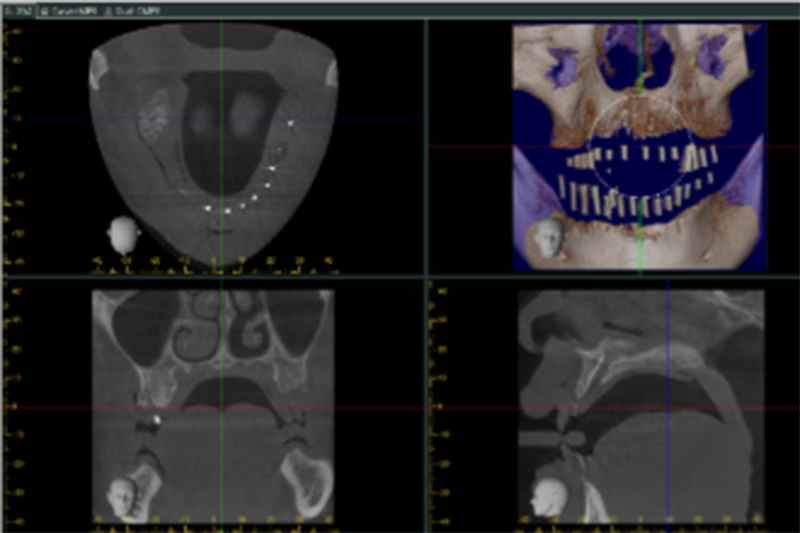

三、拍CT電腦斷層掃描

確認上下顎骨頭的寬度與高度、植體的分布與數量。

CT拍完後,會融合模型分析的數據,顯示出植體模擬位置。